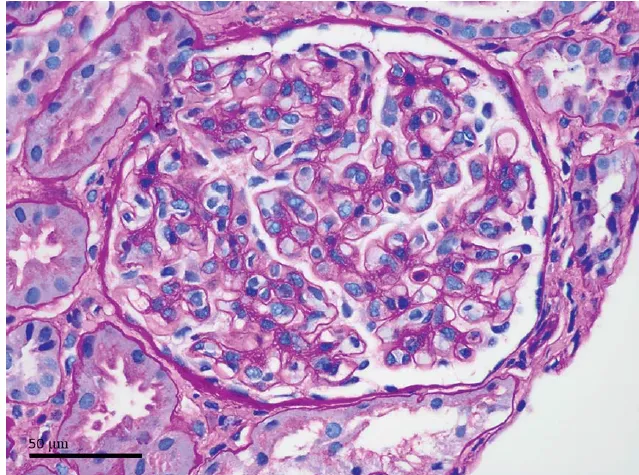

Na admissão apresentava elevação da proteína C reativa (30 mg/L) e ressonância magnética cerebral (Figura 1)

exibindo múltiplas lesões na substância branca, levantando uma suspeita de infecção do sistema nervoso central. Depois de coletar sangue e amostras de líquido cefalorraquidiano para estudo microbiológico, tratamento empírico com ceftriaxona, ampicilina e aciclovir foi iniciado, sendo optado por suspensão do micofenolato de sódio e redução dos níveis de FK (alvo de 4–5 ng/ml).